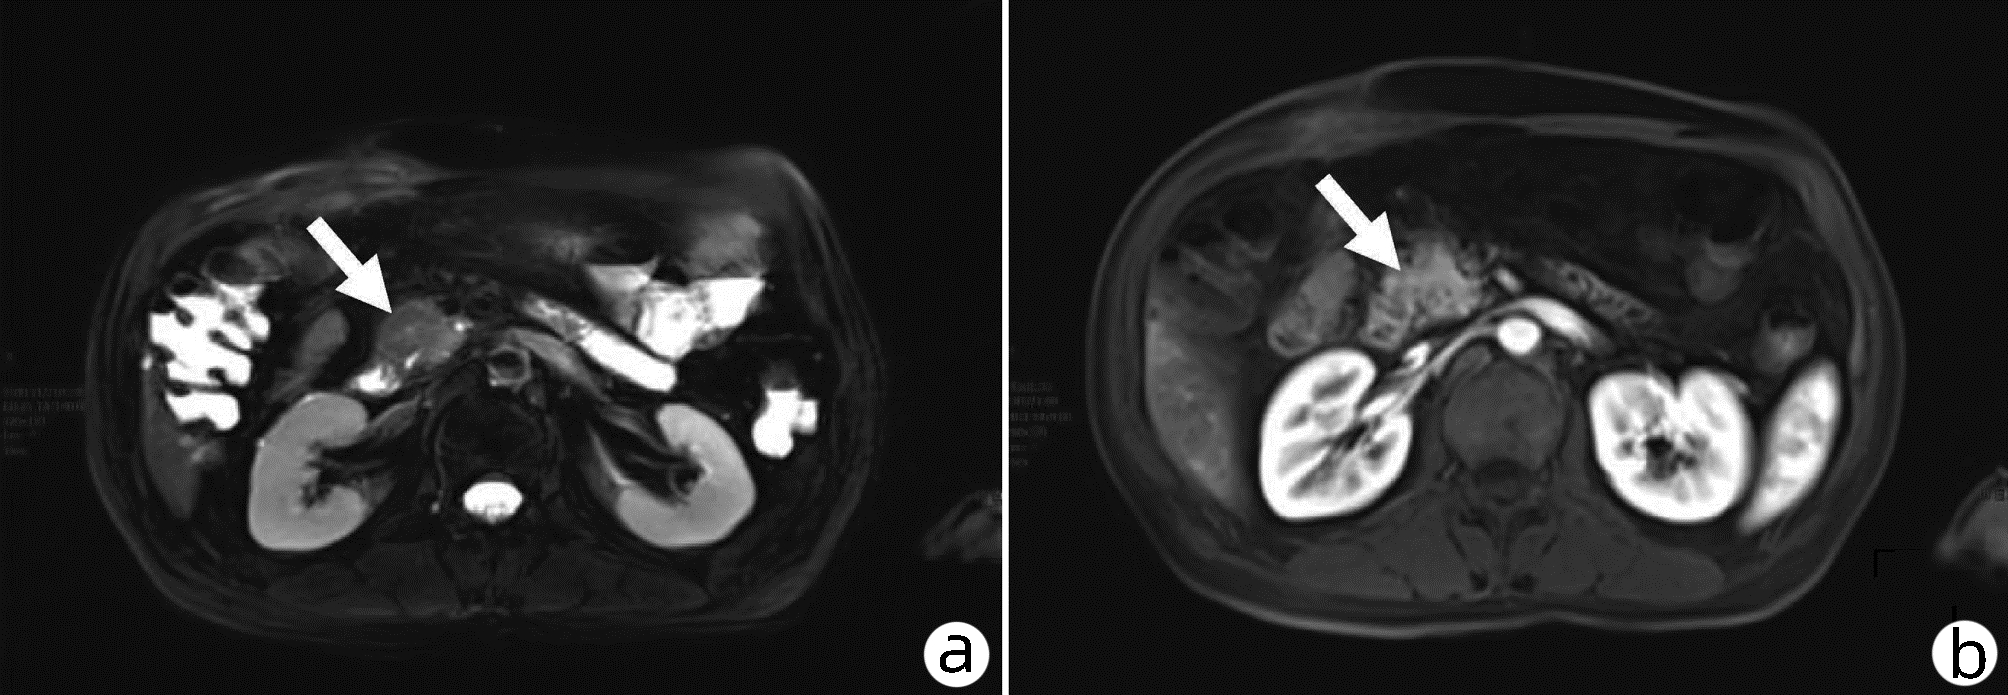

磁共振IDEAL-IQ技术对急性胰腺炎患者脂肪与铁沉积的诊断效能分析

范慧芳, 陈强, 原小军, 罗琳

2022, 38(10): 2320-2324. DOI: 10.3969/j.issn.1001-5256.2022.10.022

摘要(1308) HTML (528) PDF (2190KB)(85)

摘要:

目的  利用IDEAL-IQ技术定量参数脂肪分量(FF)和弛豫率(R2*)对急性胰腺炎(AP)患者胰腺内脂肪沉积和铁沉积进行量化评估,评价其诊断AP的效能。  方法  纳入2020年10月—2021年10月于内蒙古科技大学包头医学院第一附属医院诊治的AP患者72例为AP组,以同期82例健康体检者为对照组。两组研究对象应用GE 3.0T MRI行腹部IDEAL-IQ序列检查,并在MR后处理工作站测量胰腺FF及R2*值。符合正态性分布的计量资料两组间比较采用t检验;不符合正态分布的计量资料两组间比较采用非参数Mann-Whitney U检验。差异有统计学意义的参数进行受试者工作特征曲线分析。以曲线下面积作为评价参数诊断效能的指标。  结果  病例组中FF值显著高于对照组(Z=-10.01,P<0.001),AP组中R2*值高于对照组,差异有统计学意义(Z=-3.73,P<0.001);而轻度与中重度AP间FF和R2*值的差异均无统计学意义(P值均>0.05);FF值和R2*值诊断AP的敏感度分别为100%、48.6%,特异度分别为90.2%、86.6%。  结论  磁共振IDEAL-IQ技术定量参数FF值诊断AP的灵敏度和特异度均较高,是诊断AP的特异性指标,具有很好的临床应用前景。